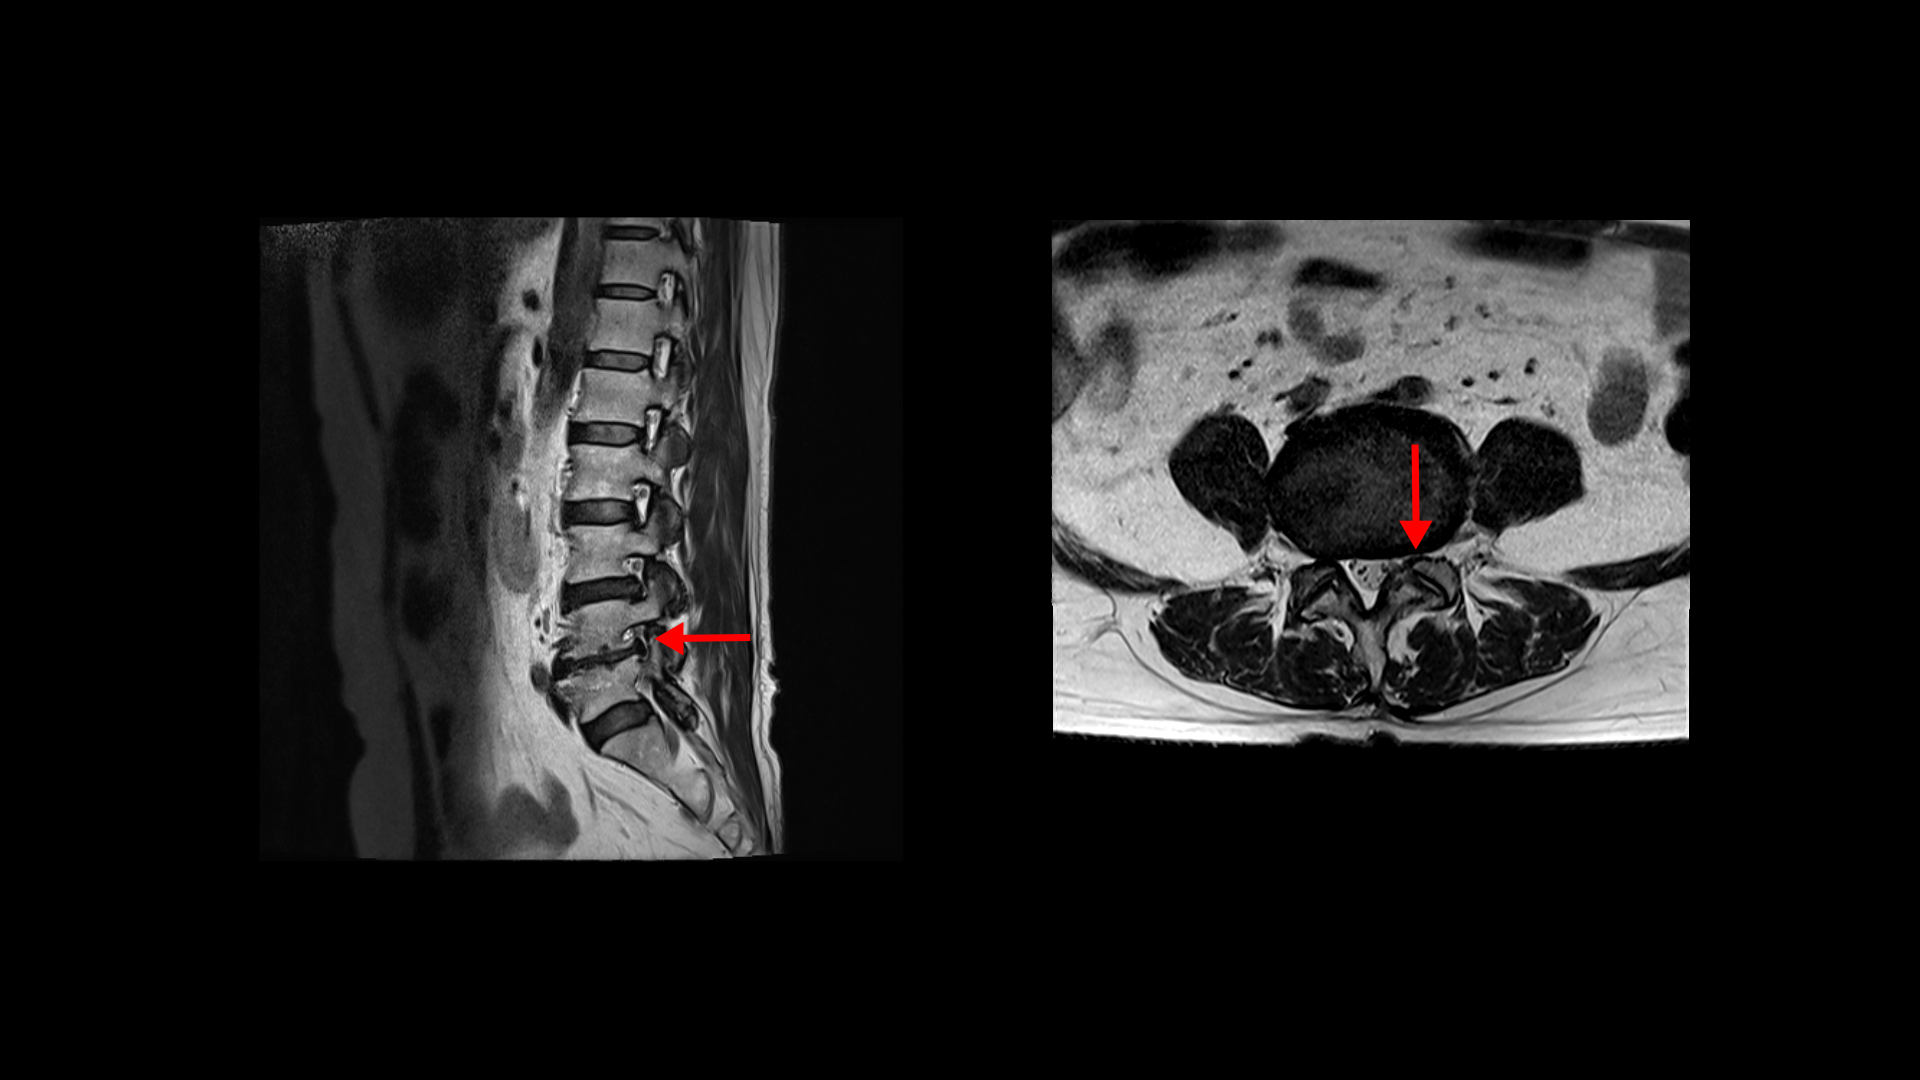

제가 먼저 이 환자분의 상태에 대해 설명드린 후 이분 말씀 더 들어보겠습니다. 이 환자분은 정말 오래된, 본인 표현으로는 30년된 심한 여러 마디의 목디스크와 또 허리에는 2마디의 퇴행성 디스크 및 추간공협착이 있습니다. 목디스크는 MRI로 보면 3번 4번 목디스크가 뼈가 심하게 자라면서 밀려나와있고 왼쪽으로 나가는 신경길을 막고 있습니다.

허리MRI를 보면 두 마디의 퇴행성디스크와 추간공협착이 있습니다.

3번 4번은 왼쪽 중앙으로 밀려나와있고

4번 5번은 왼쪽 신경이 빠져나가는 추간공이 뼈가 자라면서 좁아져 추간공협착이 있습니다.

또 왼쪽 후궁에는 과거에 받은 수술의 흔적도 보입니다.